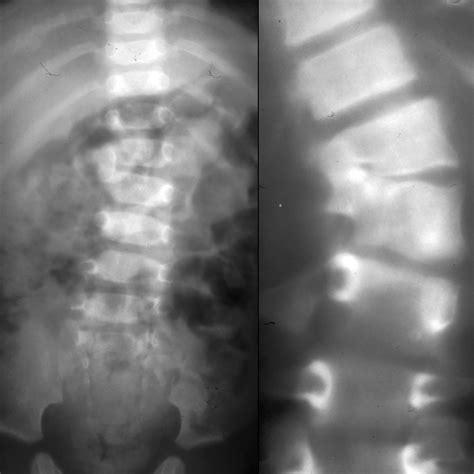

New Traumatic Scoliosis Research Shows Non-surgical Recovery Is Possible

Traumatic scoliosis – Artofit